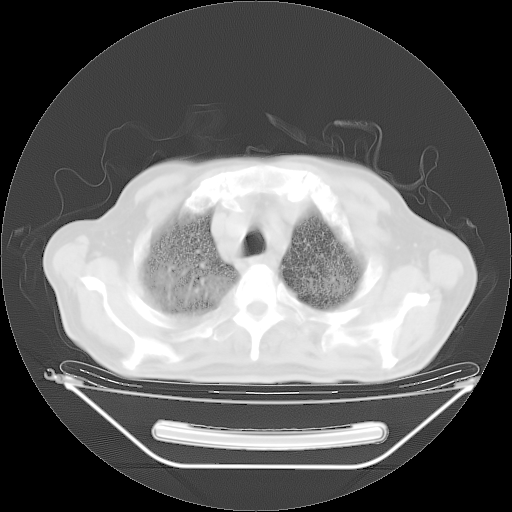

今天复查肺部CT,发现双肺广泛磨玻璃样改变。所以我把3月19日和5月9日相隔50天的肺部CT上传。请大家会诊。

5月9日肺部CT(在4月27日齐鲁医院肺部CT描述部分肺组织磨玻璃样改变,12天后肺组织广泛磨玻璃样改变)

2009年5月9日肺部CT

大致读了系列胸部CT:纵隔窗无明显异常,肺窗:从4、27至今:主要是双肺中下野外带可见毛玻璃样改变,目前处于急性肺泡炎阶段,至于原因考虑1、结替组织或胶原血管性疾病所致?2、恶性疾病如恶组在肺部所致的表现或细支气管肺泡癌?3、药物或其它原因如肺蛋白沉着症所致肺泡炎目前不太可能?总之,明天就去请我院的呼吸科、感染科、血液科和临免专家会诊哈。